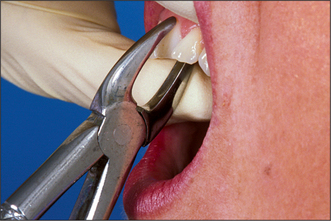

These forceps can be applied to the long axis of anterior teeth, gaining access by the patient opening their mouth fairly widely (Fig. 4.4). However, if one were to attempt to use these forceps on an upper first premolar, there is a risk of traumatizing the lower lip. Forceps for use in the upper jaw further back than the canine have a curve in the beak (Fig. 4.5), which keeps them above the lip when they are in the long axis of the tooth. The beaks of these forceps are also concave on their inner aspect to fit the root of upper premolars.

Fig. 4.4 Application of upper straight forceps to an incisor.